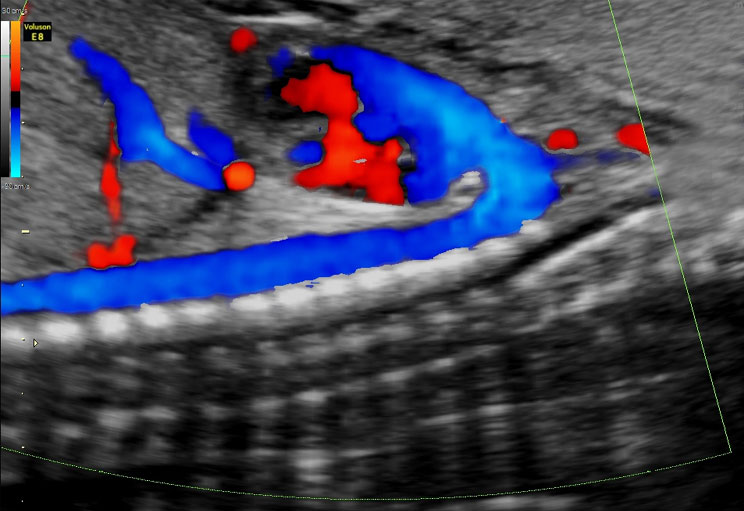

Hierbei handelt es sich um eine Methode, bei welcher die Blutströmungsgeschwindigkeit in Blutgefäßen gemessen wird.

Dies kann z.B. zur Verfeinerung von Untersuchungen, etwa der des kindlichen Herzens, der Beurteilung der Mutterkuchenfunktion und der Funktion der mütterlichen Gefäße herangezogen werden.

Das Einsatzgebiet ist vielfältig und trägt besonders zur Sicherheit von Mutter und Kind in der letzten Phase der Schwangerschaft bei.

Viele potentielle Risiken werden erkannt und behandelt, bevor sie überhaupt für Mutter oder Kind Bedeutung erlangen (Beispiele: Plazentainsuffizienz/Gestose/Notching/Normal). - 6. Herzecho